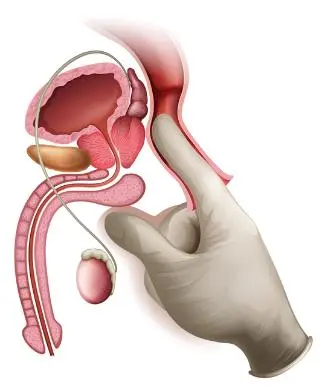

前立腺の病気 さくまクリニック

前立腺マッサージは医療行為 残尿感や排尿痛に悩む男性が急増 その不快感は前立腺炎かも ライフ 文化 ニュース 週プレnews 週刊プレイボーイのニュースサイト

前立腺の病気 さくまクリニック

前立腺を学ぼう 男のストレスと慢性前立腺炎 扶桑薬品工業株式会社